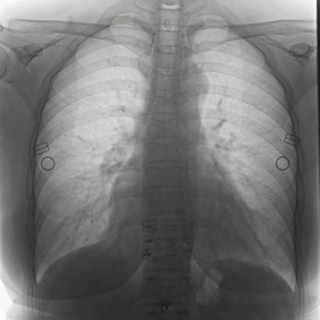

04百微平板,高清成像

普利德多功能動態(tài)DR采用100μm動態(tài)平板探測器,實(shí)現(xiàn)5.0lp/mm超高分辨率成像,大幅提升細(xì)節(jié)檢測能力;動態(tài)檢查幀率高達(dá)30幀/秒,有效避免漏診、誤診;靜態(tài)攝影有效像素高達(dá)1800萬,較之于傳統(tǒng)900萬點(diǎn)片像素,圖像細(xì)節(jié)更加清晰細(xì)膩,有助于醫(yī)生準(zhǔn)確判斷病灶的位置、形態(tài)和大小,為急診救治提供可靠依據(jù)。